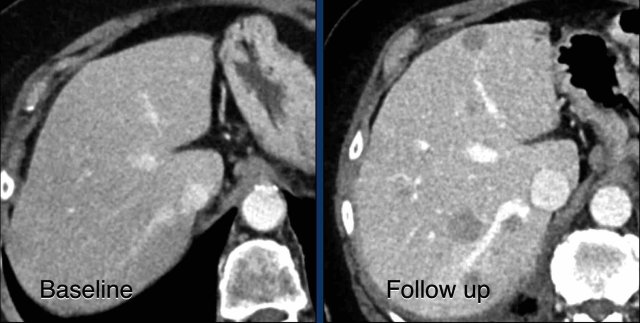

Here another example of progression of non-target lesions.

CT images in a 73-year-old male with progressive liver metastases of colorectal carcinoma.

At baseline the liver metastases were too small to be used as target lesions and consequently they were used as non-target lesions.

At follow up there is unequivocal progressions.

Unequivocal progression of non-target lesions means progressive disease, even if there is partial response or even disappearance of the target lesions.